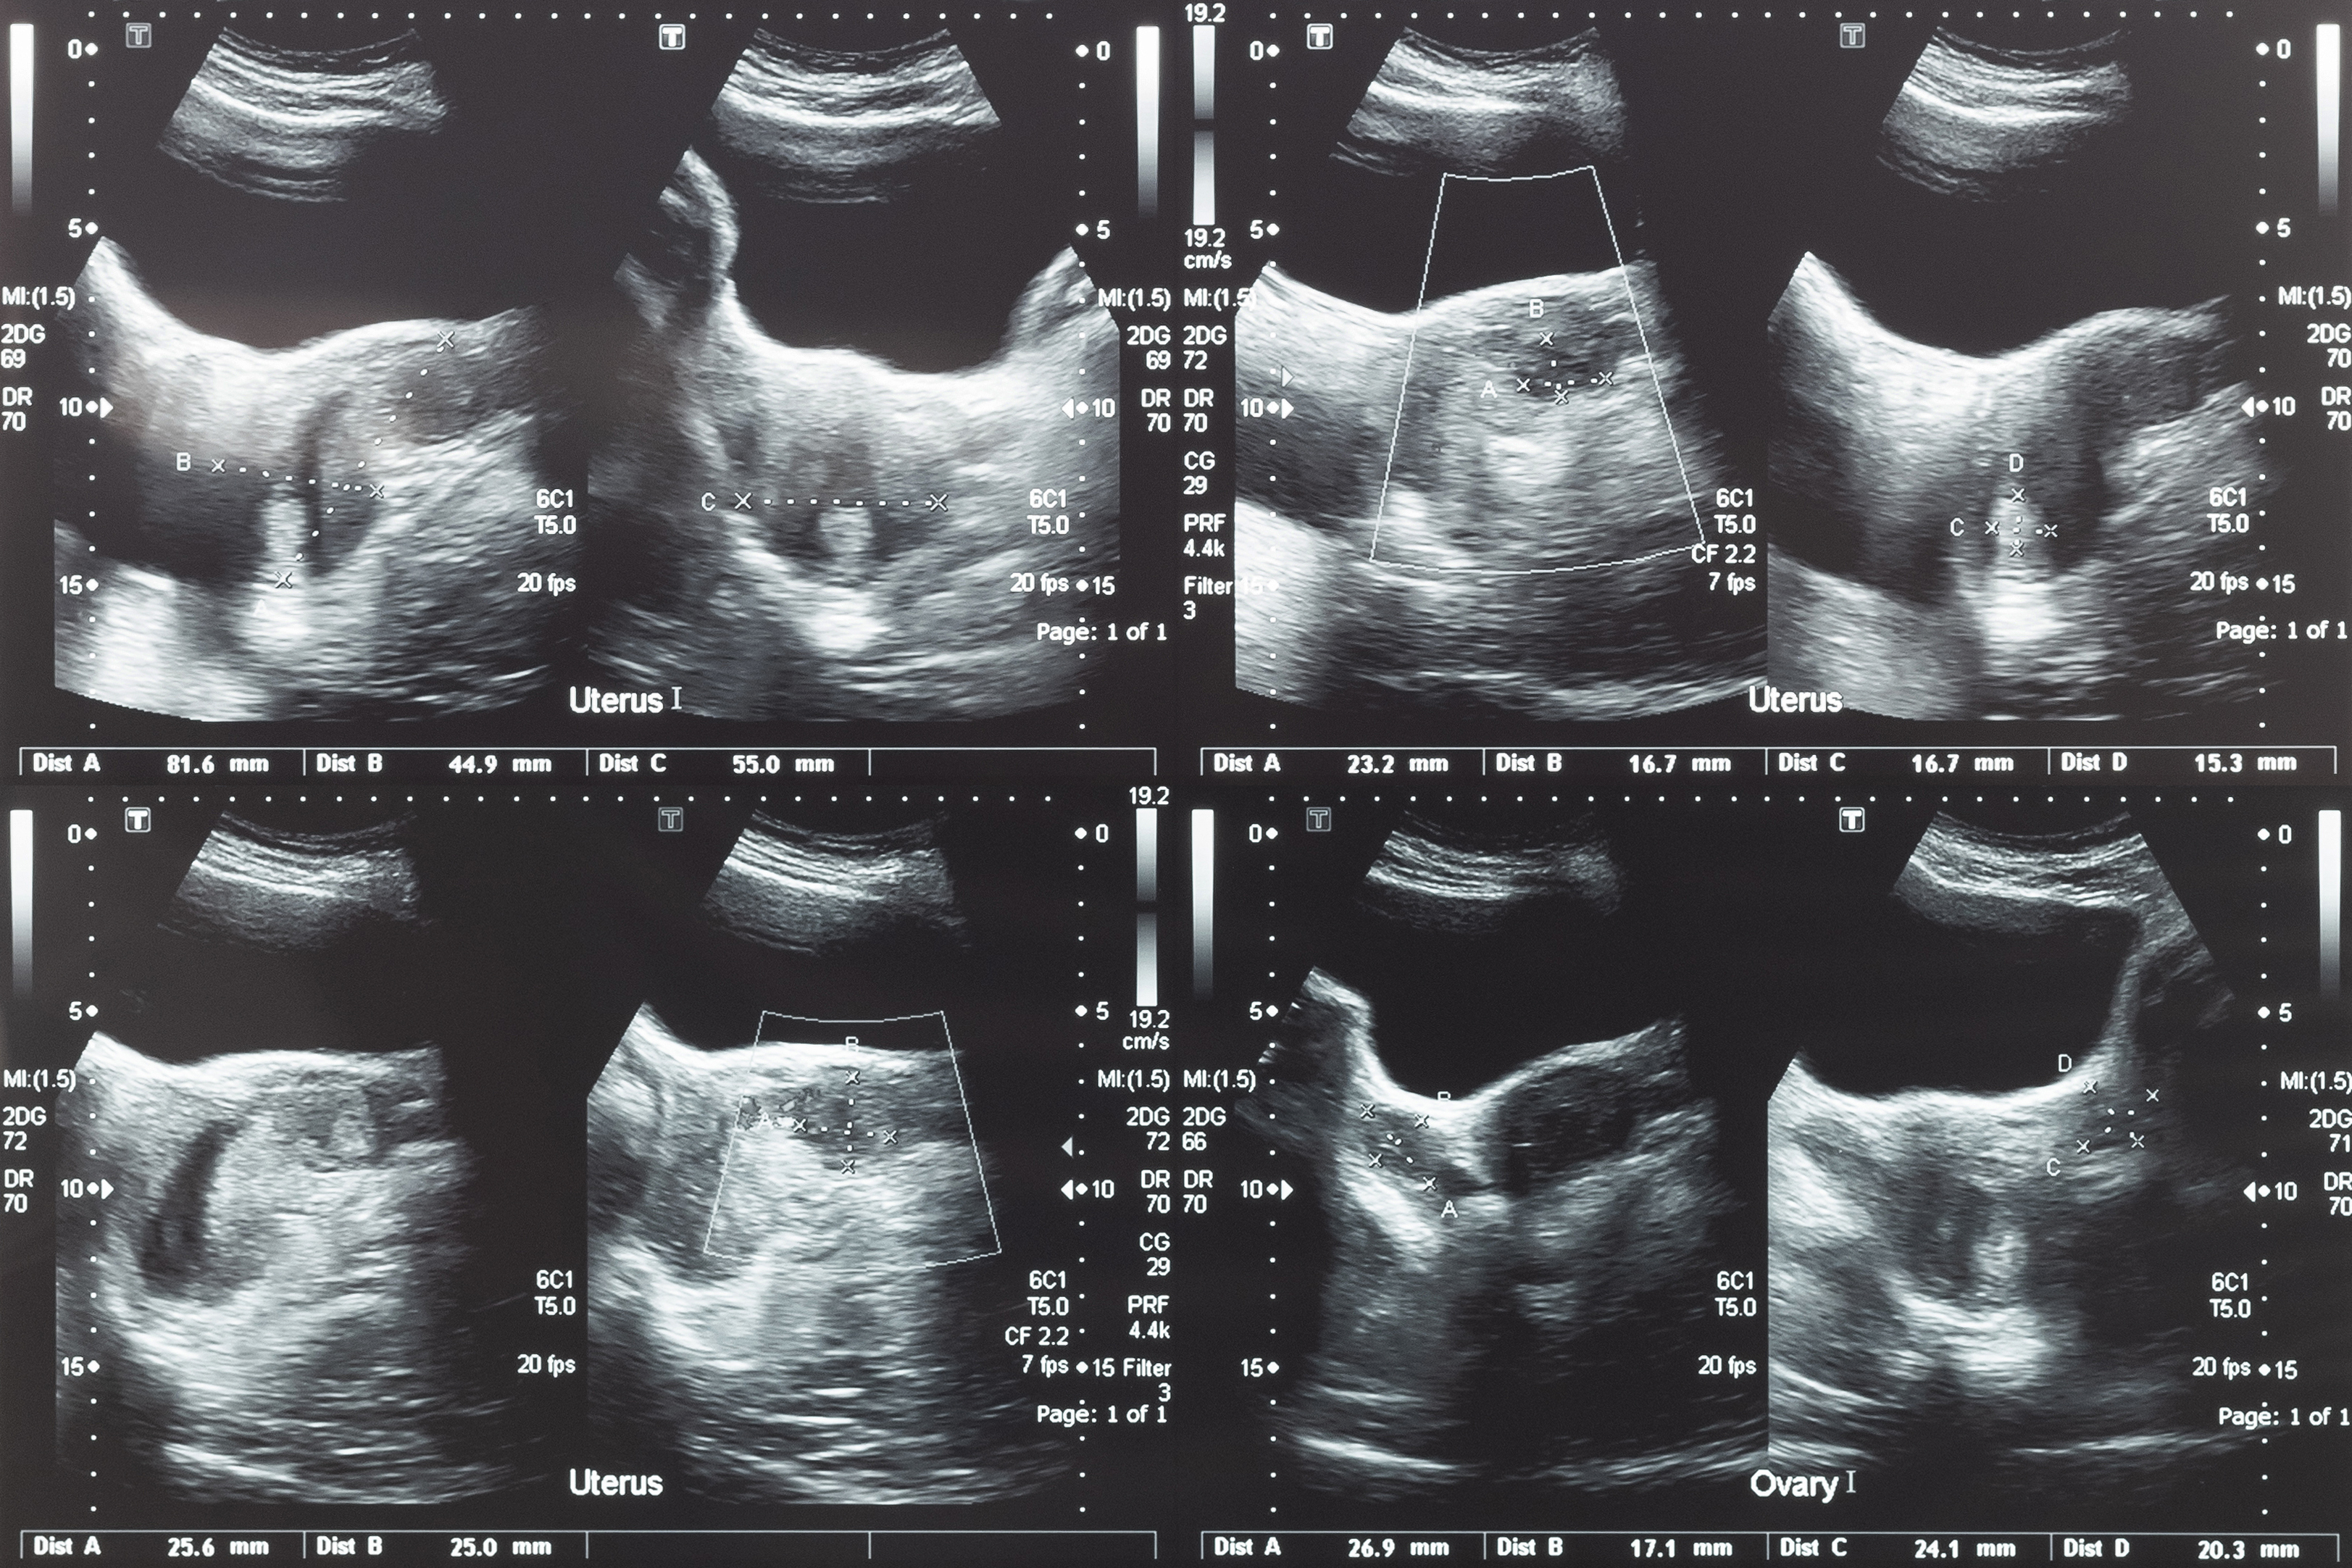

Uterine Cancer, also known as cancer of the womb, is cancer that arises in the uterus – a hollow organ about the size and shape of an upside-down pear.

The bulk of the uterus is smooth muscle tissue, which is called the myometrium. The uterus sits low in the abdomen between the bladder and rectum and is held there lightly by muscle. It is joined to the vagina by the cervix, which is the neck of the uterus.

There are several different types of cancers of the uterus depending on which cells the cancer affects and the part of the uterus in which it grows. Most cancers of the uterus arise in the lining of the uterus (the endometrium). Other uterine cancers can also develop in the muscle layers of the uterus.